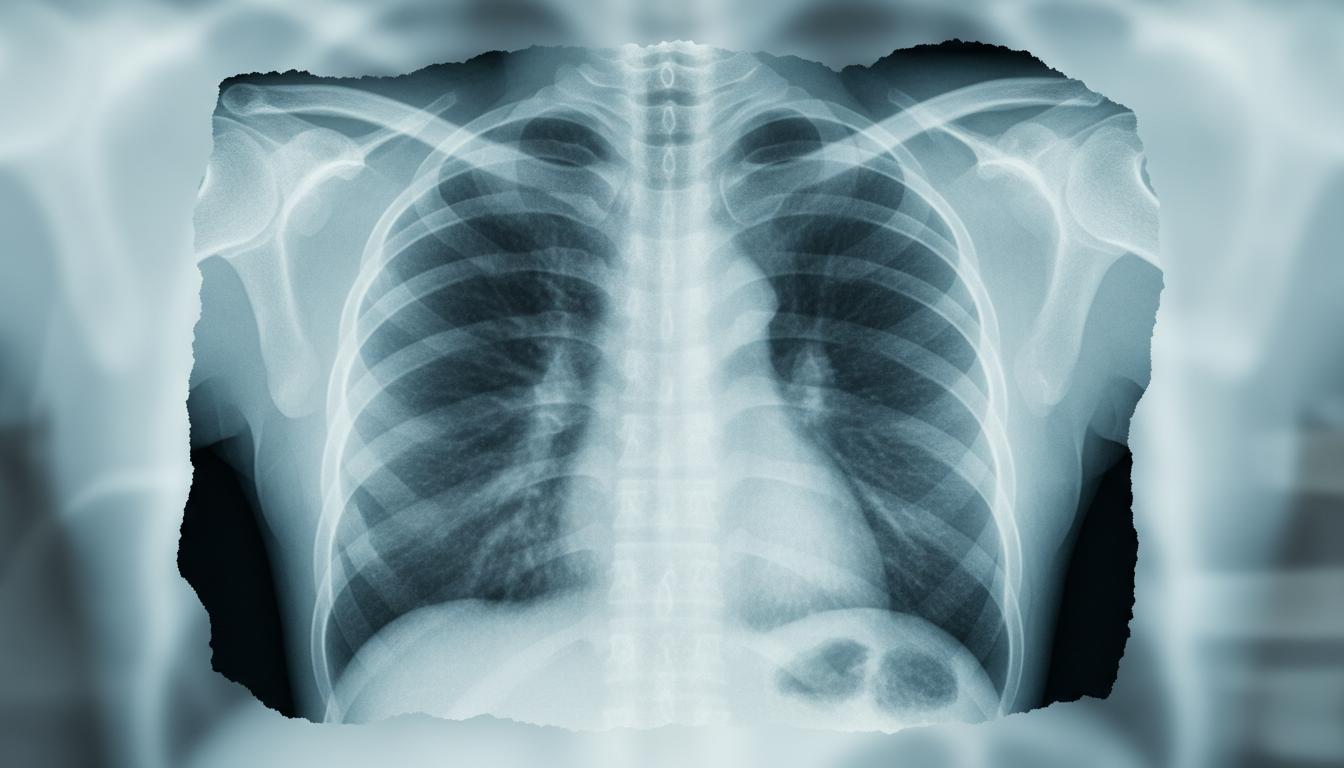

Nowoczesna diagnostyka zapalenia płuc opiera się na trzech filarach: badaniu fizykalnym, diagnostyce obrazowej i badaniach laboratoryjnych. Lekarz najpierw osłuchuje klatkę piersiową stetoskopem, poszukując trzeszczeń, świstów czy osłabionego szmeru pęcherzykowego. Jednak wątpliwości rozwiewa często dopiero zdjęcie RTG klatki piersiowej, które uwidacznia obszary konsolidacji, wysięku czy obrzęku.

- RTG (rentgen klatki piersiowej): Podstawowa metoda obrazowania, wykrywa nacieki i wysięk.